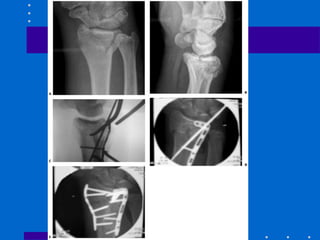

Fixação interna - Placa volar

• Devido às complicações antes citadas,

muitos autores têm indicado fixação das

fraturas dorsalmente deslocadas através de

abordagem palmar - não dá apoio contra

dorsal deslocamento

• cuidar último parafuso para não penetrar

articulação

• Não pode haver cominuição dorsal

• Abordagens

# entre flexor radial do carpo e artéria radial

– melhor exposição para coluna

radial(estilóide)

#entre flexores e feixe ulnar – acessa coluna

intemediária(fossa lunar)

• Fig 26-25

• Fig 26-26

• Fig 26-27

• Fig 26-28

Fratura Articular Palmar

Cisalhamento

• Redução anatômica articular e compressão

através da fratura

• Placa de apoio palmar é ideal

• Cuidar: placa deve apoiar fossa lunar e se

fratura dorso radial a placa submoldada

pode deslocar dorsalmente o fragmento

distal

• Fig 26-29

A,B Tração não reduziu córtex palmar C,D Placa

volar com cominuição estilóide radial residual E,F

placa de coluna radial utilizada( pode ser Fio K)